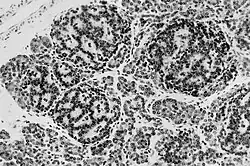

Zespół Beckwitha-Wiedemanna charakteryzuje się zwiększoną predyspozycją do nowotworów zarodkowych. Częstość nowotworów w BWS wynosi około 7,5%, 10% u pacjentów z hemihipertrofią. Częstsze jest występowanie: nerwiaka płodowego (neuroblastoma), guza Wilmsa (nephroblastoma), hepatoblastoma i mięsaka prążkowanokomórkowego (rhabdomyosarcoma).